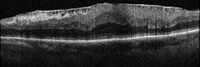

La angiografía fluoresceínica tiene un papel destacado en los pliegues de reciente aparición porque revela el patrón característico de hiperfluorescencia en las crestas combinada con hipofluorescencia en los valles (Figura 1). La tomografía de coherencia óptica (OCT) tiene una especial utilidad en diferenciar los pliegues coroideos de los pliegues retinianos secundarios a patología de la interfase vítreo-retiniana (Figura 2A y Figura 2B)3. Los últimos son más finos, irregulares y menos pigmentados; no se visualizan en la angiografía y la OCT revela su causa (membrana epirretiniana, tracción vítreo-macular…). Recientemente se ha demostrado que los grosores coroideos subfoveales medidos con OCT son mayores en los pacientes con pliegues en comparación con la población normal4. La autofluorescencia es una técnica útil y además no invasiva en la demostración del típico patrón que muestra la angiografía. Se diferencia de ella que el patrón de líneas claras y oscuras aparece de forma inversa (las crestas son hipoautofluorescentes y los valles hiperautofluorescentes)5.

Figura 2A. OCT-SD pliegues retinianos producidos por una membrana epirretiniana.